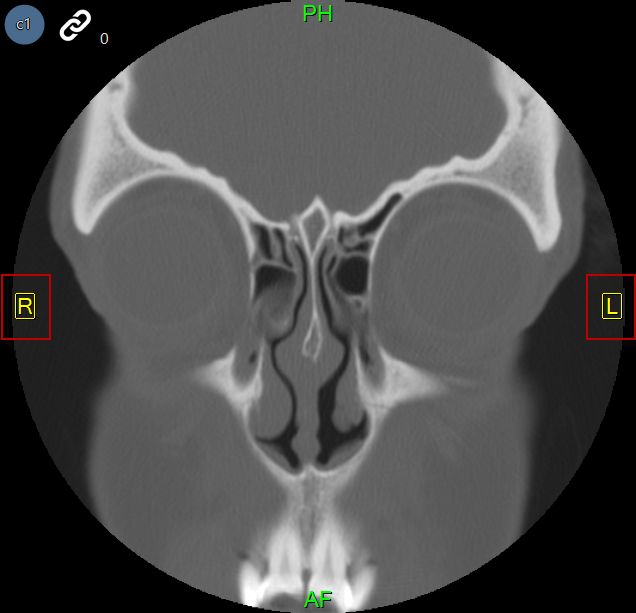

Az alábbi képek egy orrmelléküregi CT-t és egy mammográfiát ábrázolnak, amelyen automatikus orientáció van alkalmazva.

Az automatikus orientáció funkció felülírja a modalitás által meghatározott alapértelmezett betegorientációt, és a felhasználó által meghatározott orientációt alkalmaz. Ha egy képen automatikus orientációt alkalmaznak, a beteg orientációs mutatói kényszerítetten a képen, sárga színnel jelennek meg.